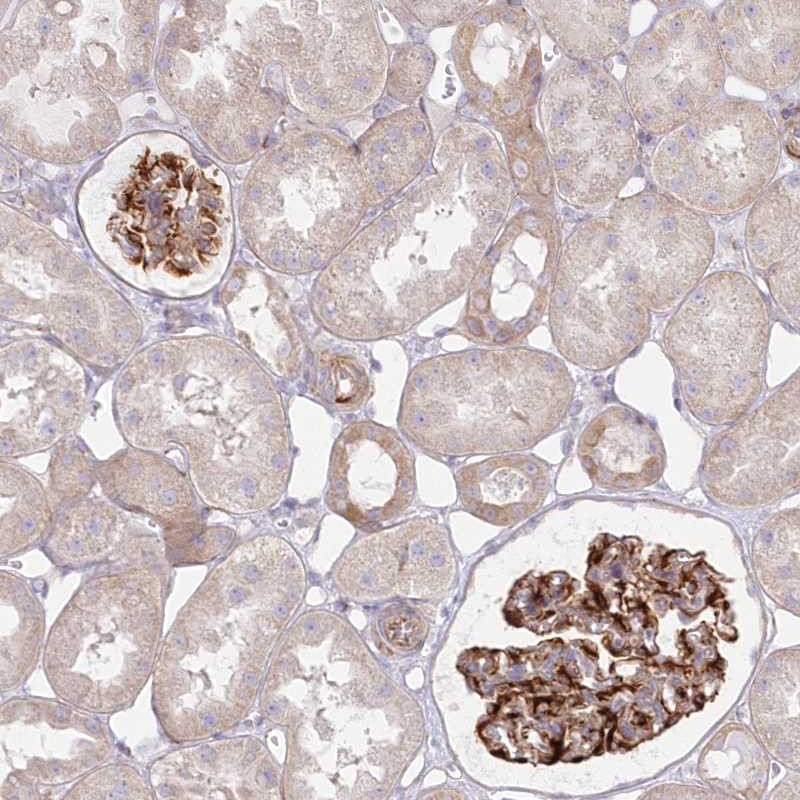

Immunohistochemical staining of human kidney shows strong cytoplasmic positivity in cells in glomeruli.